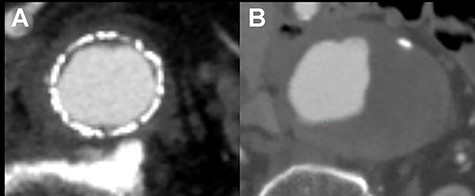

A 76-year-old man was incidentally diagnosed with a left CIAA by abdominal ultrasonography, with computed tomography (CT) demonstrating a left CIAA measuring 4.5 cm in diameter (Fig. 1A). The patient was referred to our hospital for surgical treatment. He had a medical history of liver cirrhosis and traumatic abdominal injury. Thus, he underwent EVAR using a GORE EXCLUDER AAA Endoprosthesis to embolize the left internal iliac artery. The postoperative course was uneventful, and postoperative CT showed no endoleak (Fig. 1B). Follow-up CT scans at 6-month, 1-year and 2-year intervals post-EVAR revealed a reduction in the size of the aneurysmal sac. However, the 3-year interval CT demonstrated an increase in the sac size (Fig. 2A). Contrast-enhanced CT and angiography revealed no endoleak but showed a dilatation of the CIAA. Therefore, the patient underwent open aortic repair of the CIAA.

CT scan showing left CIAA (A). Contrast-enhanced CT demonstrating no endoleak after EVAR using a GORE EXCLUDER AAA Endoprosthesis to embolize the left internal iliac artery (B).